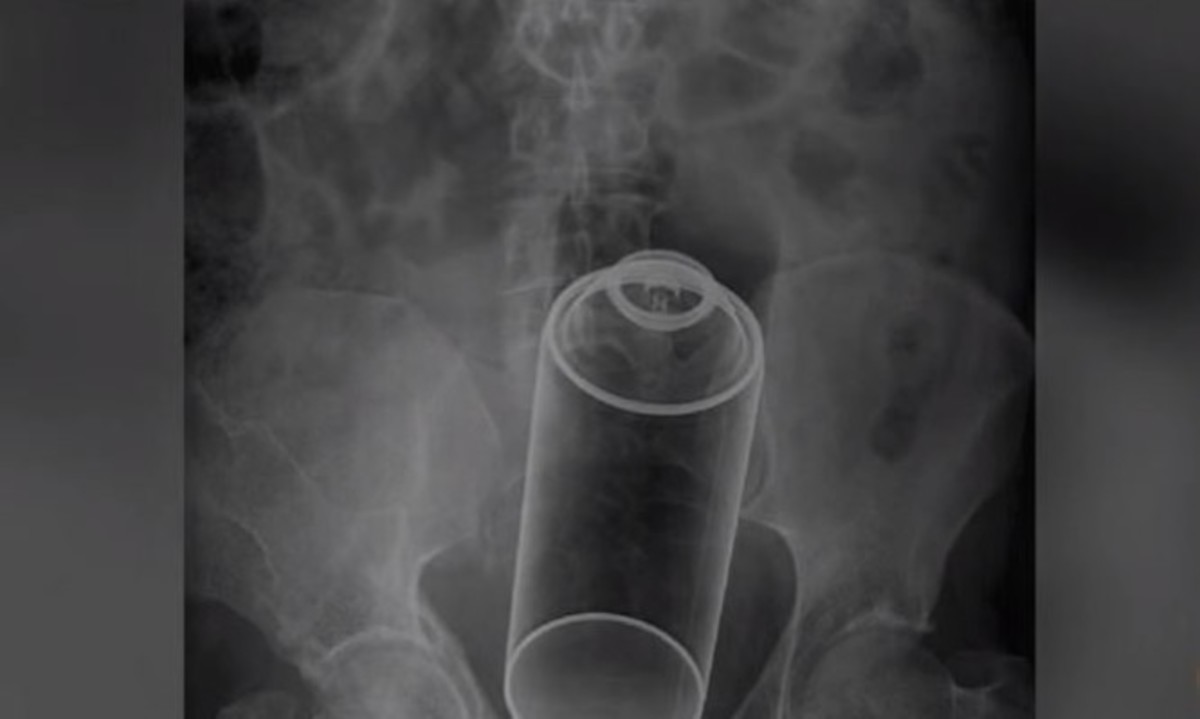

Το συγκεκριμένο βίντεο έχει σαρώσει στο διαδίκτυο τους τελευταίους μήνες, αφού αποτυπώνει με γραφικό και ταυτόχρονα ενημερωτικό τρόπο το ποιες είναι οι σωστές κινήσεις που πρέπει να κάνει κάποιος, προκειμένου να βοηθήσει ένα μικρό παιδί που πνίγεται, επειδή κατάπιε κάποιο αντικείμενο.